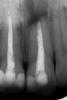

sergev Опубликовано 19 мая, 2012 Автор Поделиться Опубликовано 19 мая, 2012 Спасибо большое за ответы. Сделали еще прицельные снимки с разных ракурсов. Они что-то меняют? Если делать резекцию, хватит ли оставшегося корня для того, чтобы держать зуб? Первый - http://www.softaffil...ev/rentgen1.jpgВторой - http://www.softaffil...ev/rentgen2.jpg Ссылка на комментарий

kriokov Опубликовано 19 мая, 2012 Поделиться Опубликовано 19 мая, 2012 да несколько меняет. Смотрел кт и ошибся , думал коронка и вкладка в зубе.Ситуация штатно развивается, надо начинать с того, что полноценно перелечивать канал зуба и оценить вместе с врачом, как потом зуб будет восстановлен вкладка + коронка или еще как. Если нормально канал удасться перелечить, длины корня хватит для устойчивости зуба. Может вообще без хир вмешательства обойтись, но все надо в динамике смотреть. Пусть лечащий врач на зуб 11 обратит внимание, там есть незначительные изменения. Ссылка на комментарий